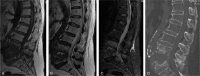

Retrospective Cross-Sectional Study.The purpose of this study was to investigate the accuracy of magnetic resonance imaging (MRI) for distinguishing between pyogenic spondylitis and brucellar spondylitis.Although pyogenic spondylodiscitis (PS) and brucellar spondylitis (BS) are common causes of spinal infections, the variety of their clinical manifestations complicates differential diagnosis. MRI may be helpful in differential diagnosis and treatment.MRI images of 64 patients who underwent MRI of the spine and with confirmed spondylitis were retrospectively reviewed. After referring to the related medical literature, we compared 32 patients with pyogenic spondylitis and 32 patients with brucellar spondylitis regarding MRI findings. Statistical analysis was performed with the chi-square test. Statistical significance was defined as P < .05.The significant differences between PS and BS on MRI findings are listed as follows (P < .05): diffuse, partial and fan-shaped hyperintense signals on middle sagittal fat-suppressed weighted images (PS: 51, 11, 3/65 vs BS:35, 18, 19/72); focal endplate destruction (PS: 9/43 vs BS:27/35); extensive end plate destruction (PS: 29/43 vs BS:8/35); ballooning change of the intravertebral space (PS: 7/32 vs BS:0/32); an inflammatory reaction line from the end plate (PS: 30/65 vs BS: 1/72); a disc invasion sign (PS: 1/28 vs BS:12/33); an inflammatory reaction line in the disc (PS: 5/28 vs BS:25/33); and 8) severe intravertebral space destruction (PS: 17/28 vs BS:12/33);MRI imaging provides useful information for the differentiation between pyogenic spondylitis and brucellar spondylitis.